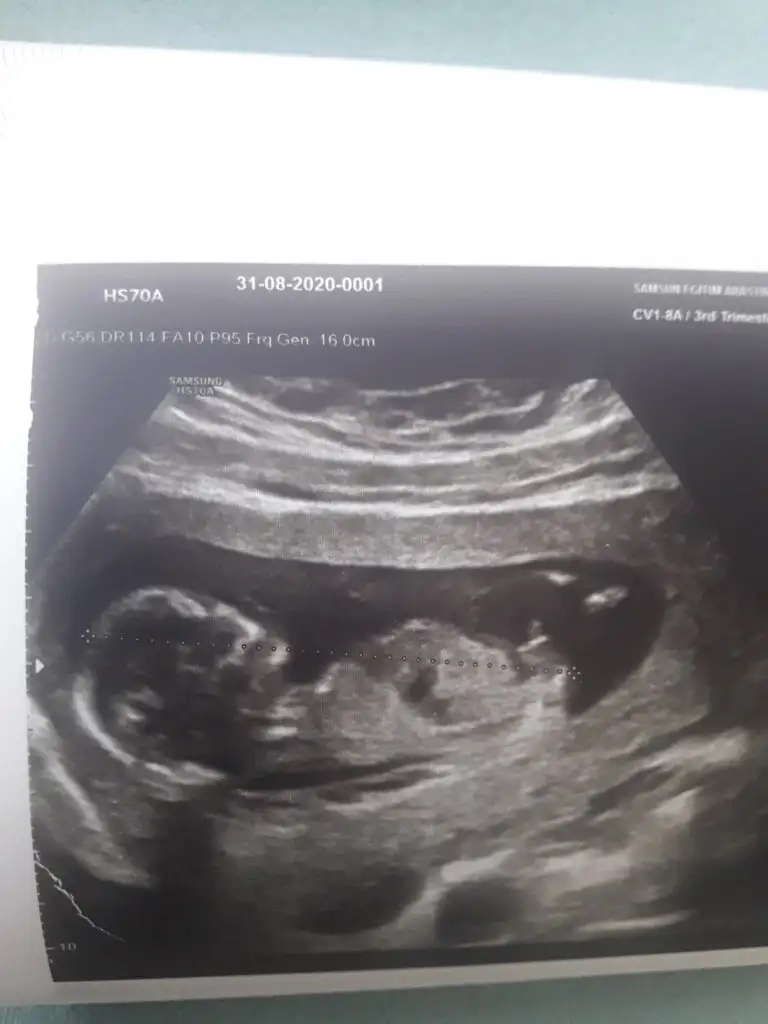

dr soylemeden siz gorun genital nub teorisi ( bebegin cinsiyeti)

Eklentiler

• Screenshot_20200829-210321.webp

Screenshot_20200829-210321.webp

15,4 KB · Görüntüleme: 65

Bu başlığı baya takip etmiştim. Bi kızım var. İkinciye hamileyim. 11+2 kontrole gittiğimde doktor ilk dakika cinsiyet tahmini ister misiniz dedi çıkıntı o kadar barizdi ki zaten o tahmin etmese ben bile ederdim. Nub çıkıntısı tam paraleldi doktor da ayrıntılı gösterdi cıkıntıyı. Çok net olarak kız çıkıntısıydı. Biz baya 2.kız geliyor diye kendimizi ona alıştırdık derken 15+2 kontrolde çok net pipisini gösterdi bizimki. Alttan üstten yandan renkli her yerden baktı doktor ayrıntılı inceledi erkek. Yani demem o ki nub teorisi bende tutmadı. İnşallah sağlıkla gelsin herkesin evladı. Herkesin gönlündekini nasip etsin inşallah.